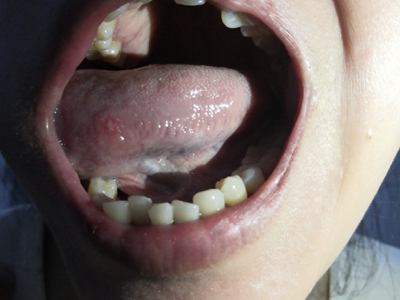

口腔溃疡为圆形或椭圆形,直径0.2-0.5cm,溃疡单个或由数个连成一片,溃疡表浅边缘整齐,外观呈灰黄色或灰白色,上覆盖黄白渗出膜,周围黏膜充血、水肿而有红晕。

皮损局部有烧灼样疼痛,于进餐时加重,影响进食、说话。严重溃疡直径可达1-3cm,深及黏膜下层甚至肌肉。